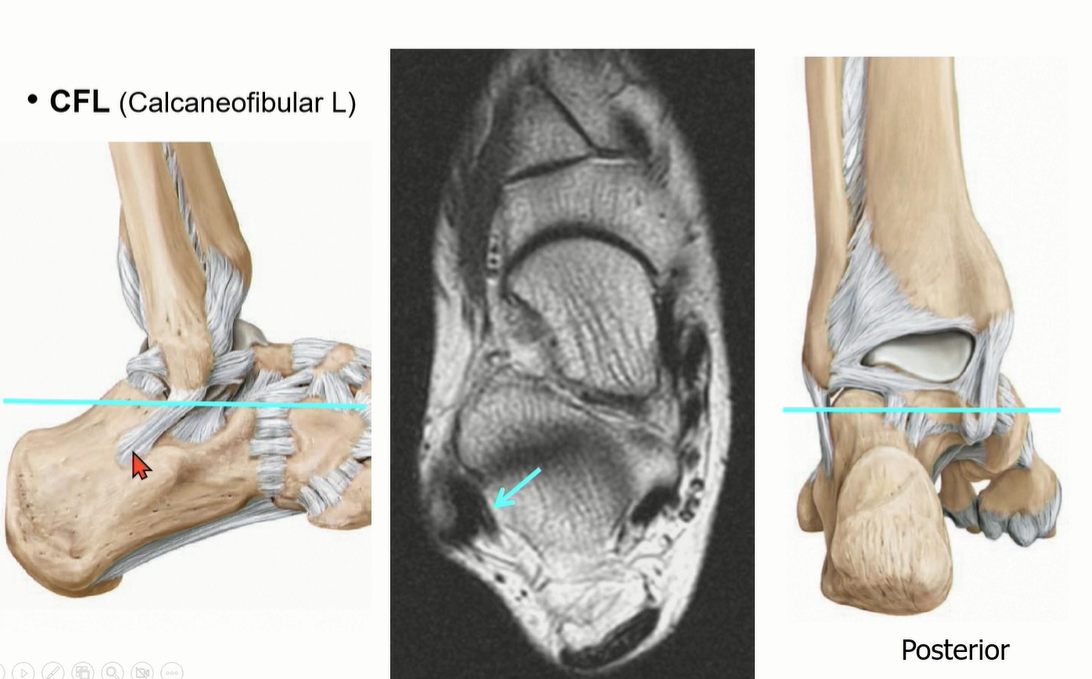

2-2 . CFL (Calcaneofibular ligament)

ATFL과 떨어져서 기시한다는 이야기도 있었지만, Just below ATFL로 이해하면 좋을 것 같다.

Peroneal tendon을 landmark로 이용해서 CFL를 찾는 것도 연습해야 함.

Axial cut과 coronal cut에서 모두 확인할 수 있는데, Axial cut의 경우에는 peroneal tendon 내부에 위치한 것을 확인할 수 있다.